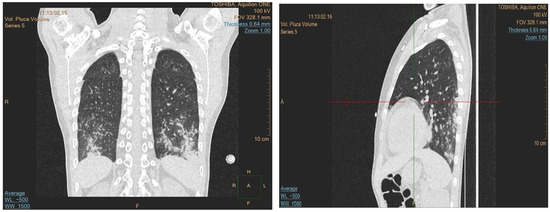

Due to the progression of the lung lesions observed in the follow-up imaging, amphotericin B was switched to isavuconazole. The patient also received broad-spectrum antibiotics and transfusions. A sinus MRI was performed to search for other potential sites of fungal involvement, which revealed suspected fungal changes in the left frontal sinus; drainage was performed, but no fungal growth was detected in the cultures. As the fever persisted despite antifungal and antibiotic treatment, an immunological cause was suspected. A control CT revealed progression of the lung lesions despite the antifungal treatment, which raised the suspicion of granulomatous lymphocytic interstitial lung disease (GLILD) (Figure 2). Bronchoalveolar lavage was performed, and the recovered fluid was sent for histopathological analysis and when stained using a Grocott stain showed no signs of fungal involvement, and no acid-fast bacteria were observed. However, cytology of the specimen showed 56% lymphocytes, 29% macrophages, 14% neutrophils, and 1% eosinophils. These histopathological findings, along with ground-glass infiltrate in a chest CT, helped diagnose the patient with GLILD, and the patient was subsequently treated with rituximab.

Figure 2. Chest CT scans with coronal and sagittal views confirming the presence of bilateral, diffuse ground-glass opacities mainly in the lower lobes, with reticular interstitial thickening.